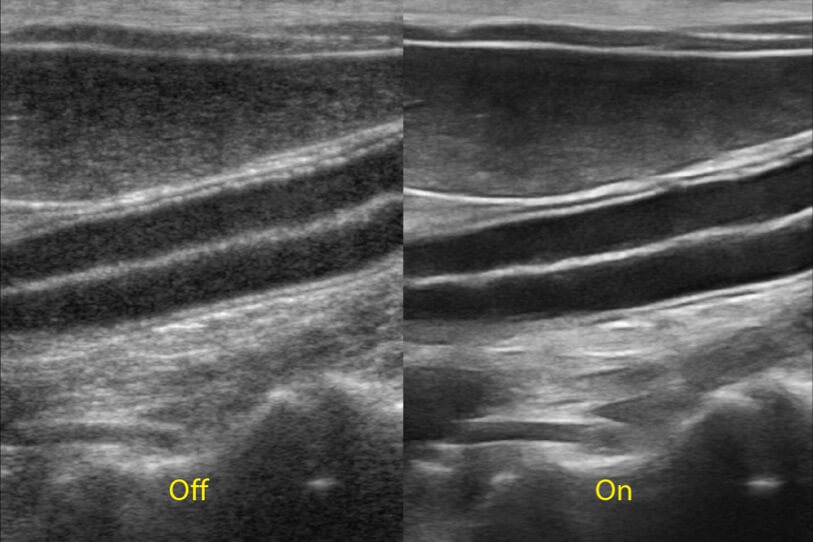

ProPet 70 進(jìn)一步提升了微米成像算法,更加注重對(duì)基礎(chǔ)原始圖像的還原和保留,在有效減少斑點(diǎn)噪聲、增強(qiáng)組織邊界顯示的同時(shí),避免過(guò)度優(yōu)化丟失真實(shí)的解剖信息。